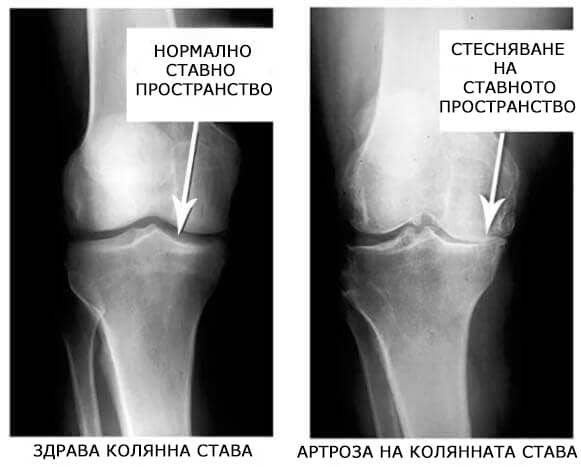

Погледнете тези снимки, виждате, че в дясната снимка липсва ставното пространство, костите се търкат една в друга, причинявайки силна болка. И този процес е много трудно да се спре!